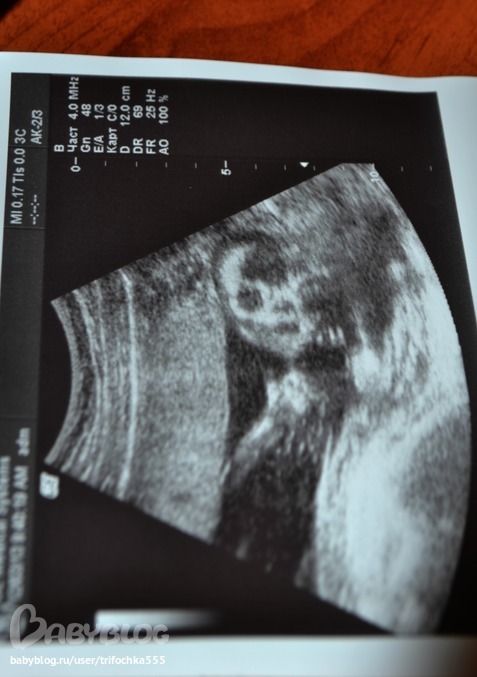

первое фото)

УЗИ, КТГ, доплерМоя Есенька)

Мой маленький инопланетянин)

Мои 300 грамм счастья)))

а скулы то какие)))

Муж сказал:"Покажем дочке ее первую фотку,но только,когда вырастет. А то по-любому испугается"

ни в коем случае не хочу обидеть. но я не понимаю на этой фотке где что :-((( мне и на моих УЗИ снимках муж пальцем тыкал "это головка", "это ножка"... Для меня до сих пор загадка, как УЗИстка мне на сроке 12 недель сказала точный пол ребенка (и ведь не ошиблась)?

у нас тоже есть подобная фотка, в таком же ракурсе)) сделана на 17 недельках! муж сказал, что малыш похож на инопланетянина)) я сказала: шшш....а то малыш обидится)))